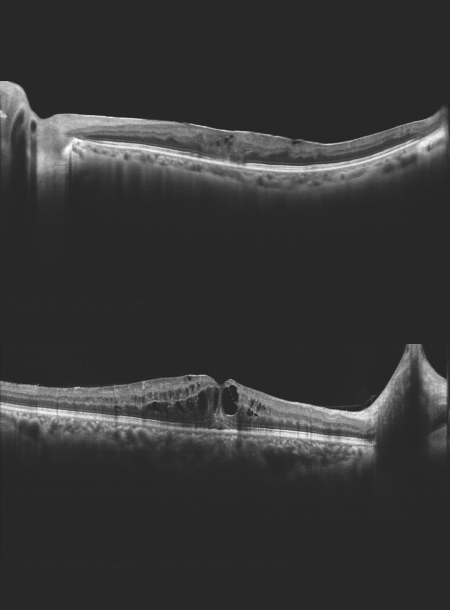

• Висока якість ОКТ-зображення

• Глибина сканування 3 мм показує деталізоване зображення склоподібного тіла, сітківки та судинної оболонки

Режим глибокої судинної томографії (DCI)

Використання глибокої судинної томографії для виявлення неоваскуляризації судинної оболонки.

High quality OCT image

Spectral domain OCT